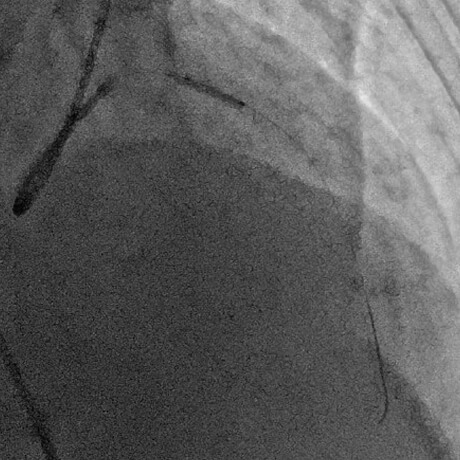

急性心筋梗塞症例へのPCI施行時の冠動脈造影画像

治療後最終の造影